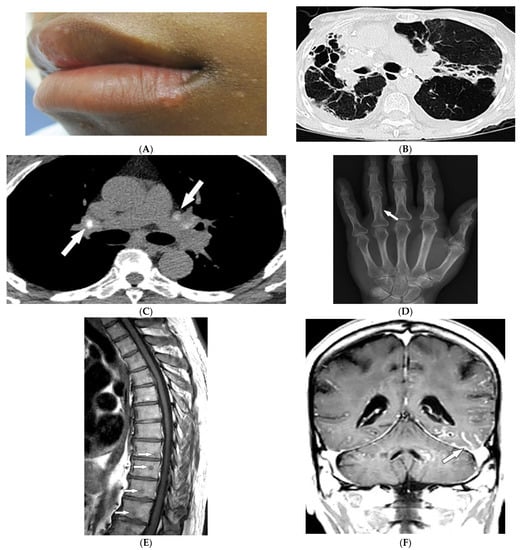

3.7. Birt–Hogg–Dube’ Syndrome

| Birt–Hogg–Dube syndrome | Fibrofolliculomas, trichodiscomas, acrochordons Lung cysts (pneumothorax) Renal cysts | Bilateral basilar predominant, thin-walled cysts abutting pleura and pulmonary vessels |